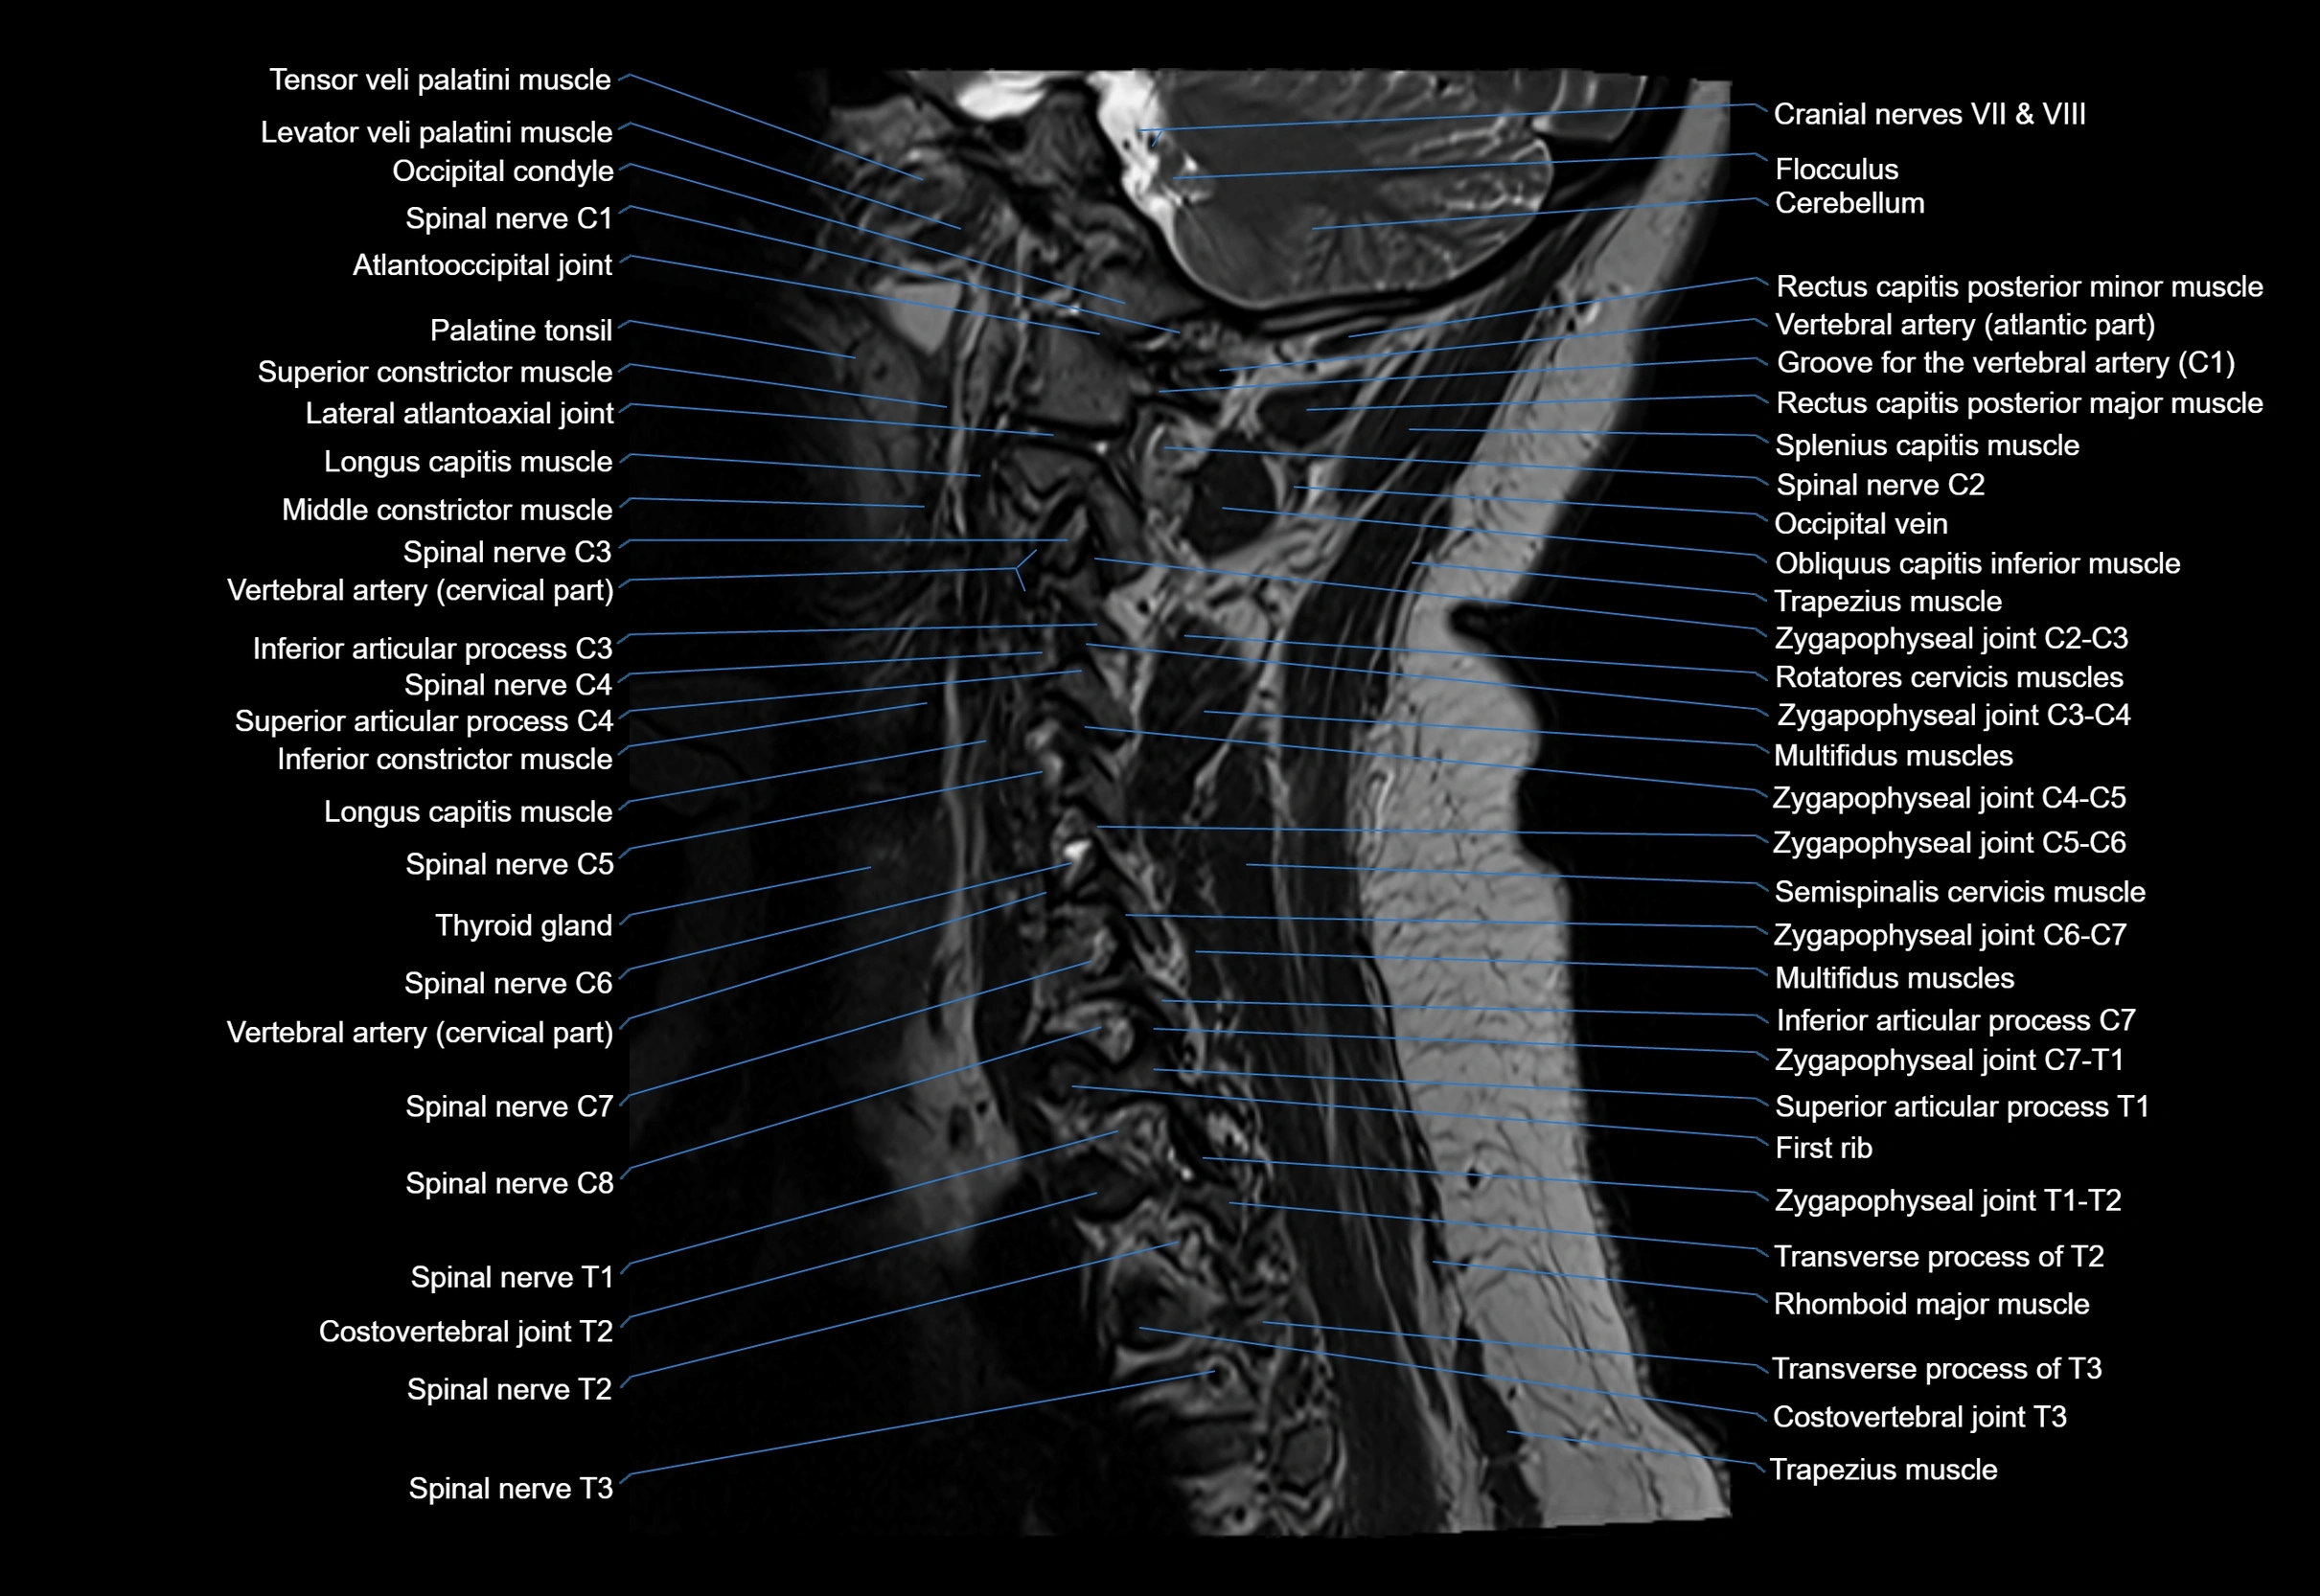

MRI image

image